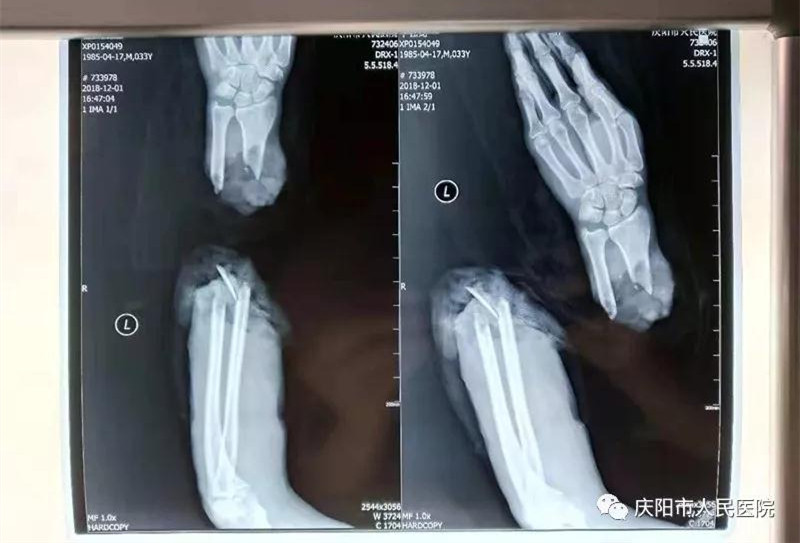

断肢再植再上新台阶。“庆阳市人民医院大夫妙手仁心,又成功完成一例断肢再植手术”手足显微外科团队在关键时刻,不惜心血和汗水连续奋战10多个小时,将完全离断的患者右前臂再植成功,刷新了断肢再植的新纪录。此病例经《陇东报》\掌中庆阳图文报道,引起社会广泛关注和点赞。截止目前,手足显微外科成功再植成活完全断离肢体数10例。